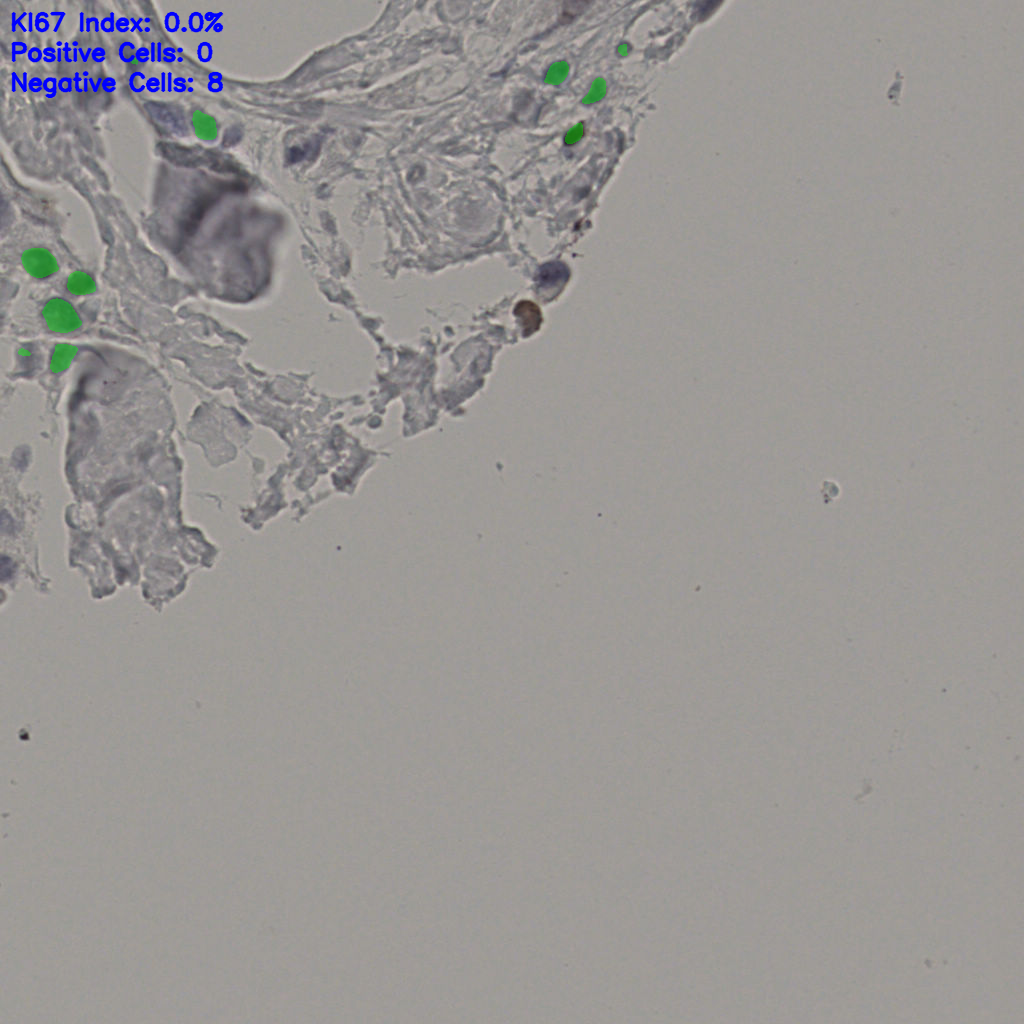

Ki67 指数

阴 19502 阳 1093